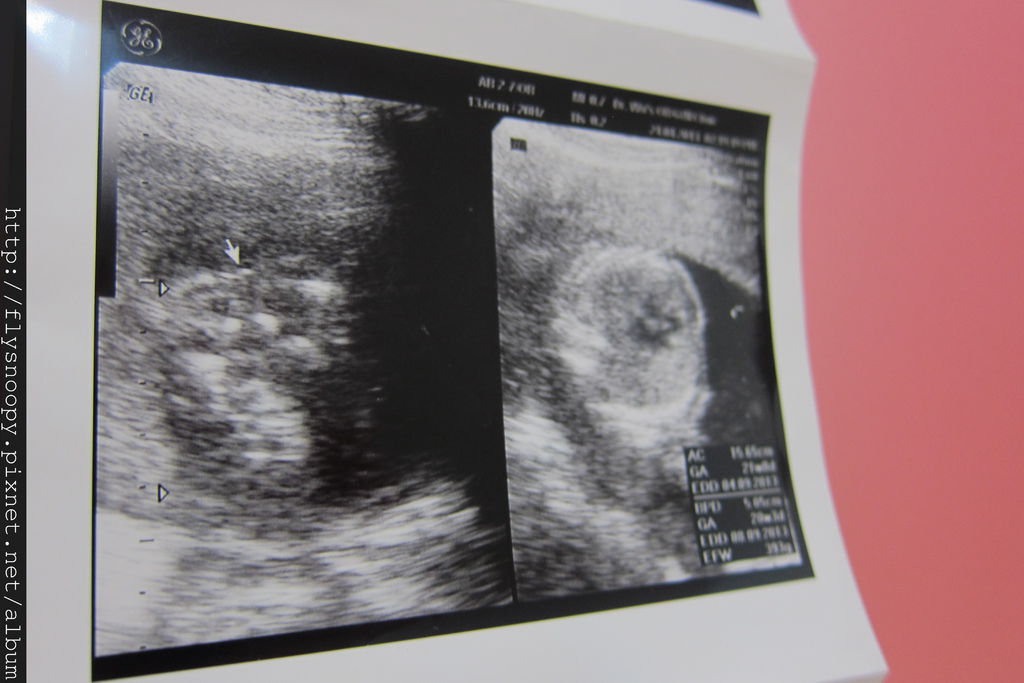

第三張我忘記是什麼^^"

第四張一樣是趴著,看不出來性別

不過醫生說應該是女生